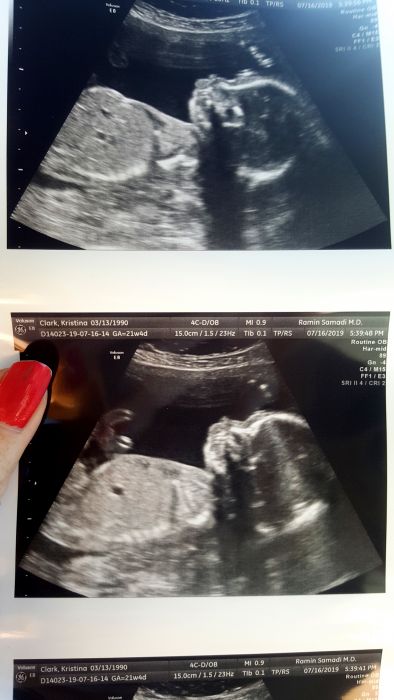

Jinak hlasim ze 2 screening probehl uspesne , trval asi jen 15min ...nic moc mi tam nepopisovali ,jen rychle klikali do pc ,ale tak aspon ze rekl na konci ze je vse v poradku a ze gratuluji. Mimoušek ma 1 poundu cili 453g :-) a je zdravy. Jinak me vychazi TP na 22.11 Richeto ,az budes zase psat tabulku :-)